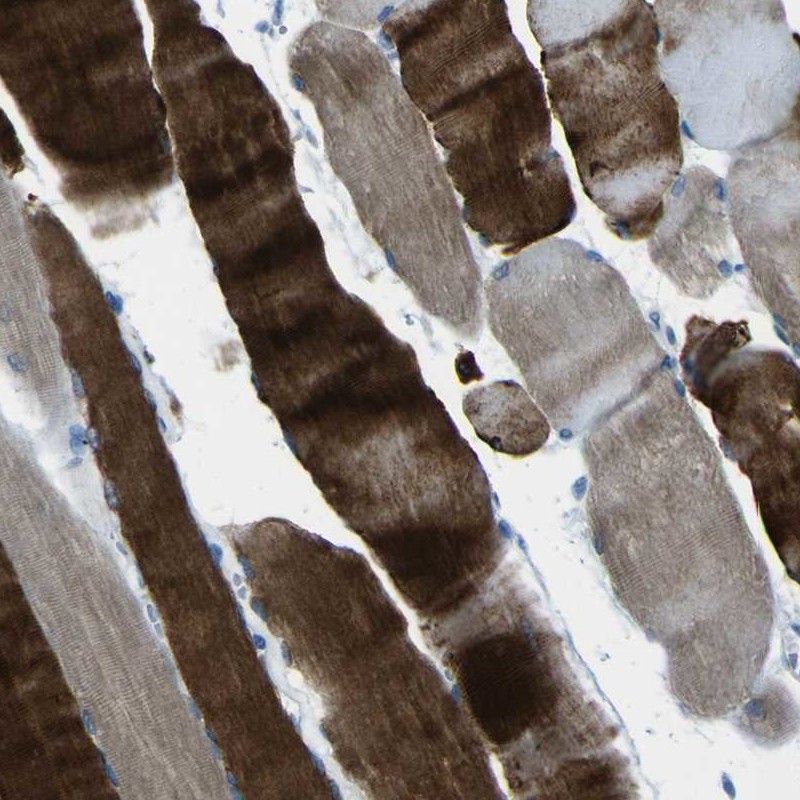

Immunohistochemistry analysis in human skeletal muscle and heart muscle tissues using Anti-PHKG1 antibody. Corresponding PHKG1 RNA-seq data are presented for the same tissues.